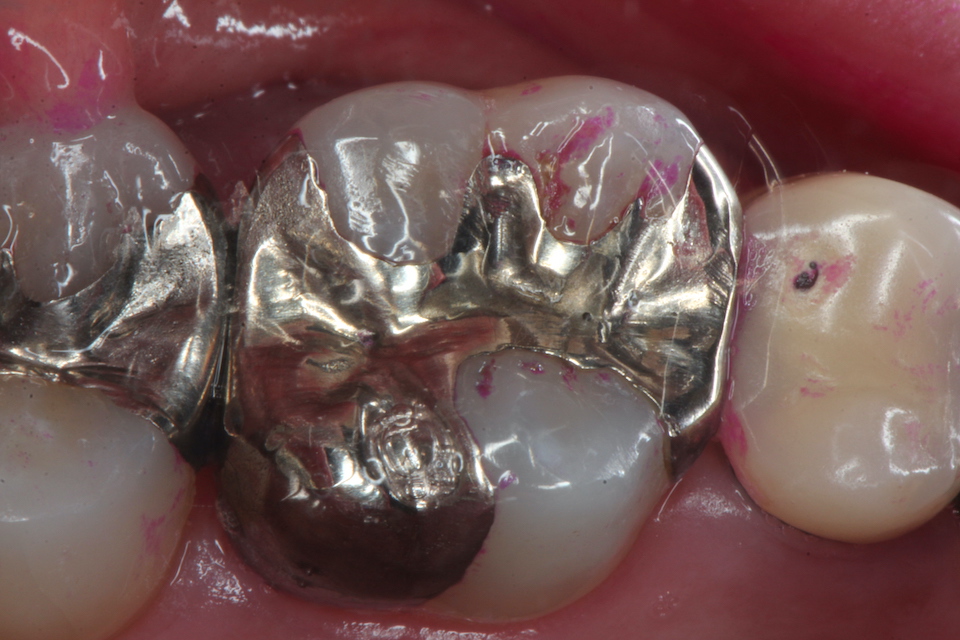

ブリッジ脱離で2次カリエス+Perでグラグ… 2025.11.01

ブリッジ脱離で2次カリエス+Perでグラグ… 2025.10.31